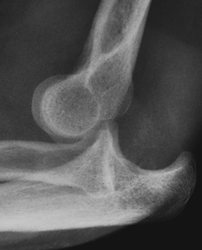

Fig 33 A. Luxación anterior del codo.

Rx lateral. Luxación anterior del codo.